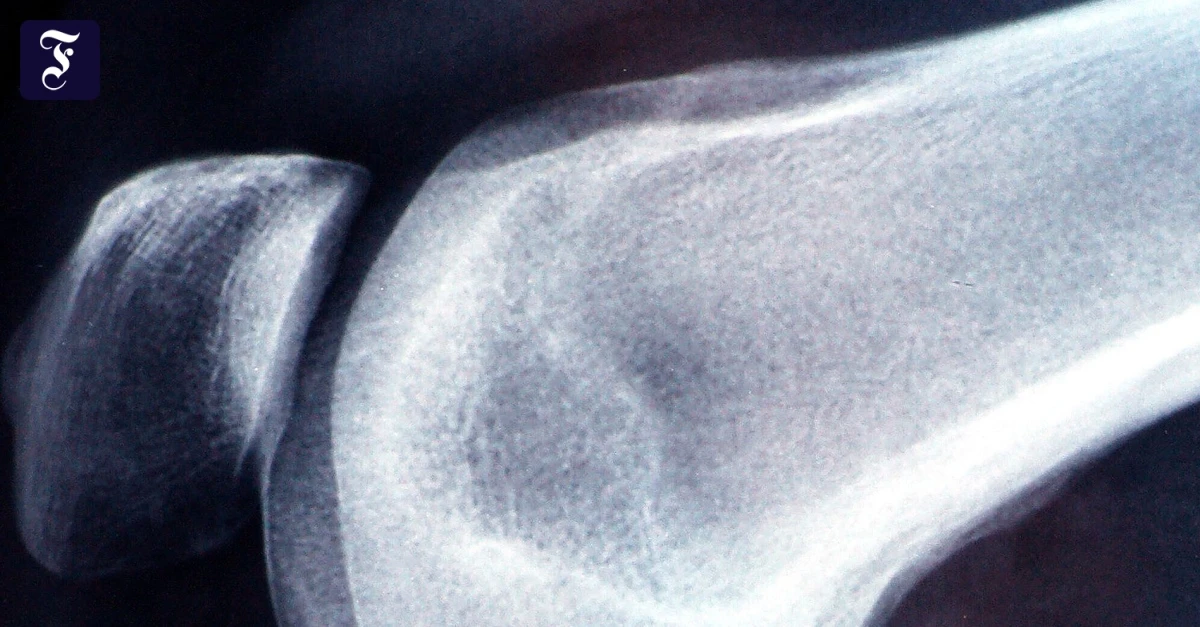

Neue Hüfte, neues Knie: High-Tech-Verfahren versprechen höhere Präzision und mehr Sicherheit beim Gelenkersatz. Aber auch die Patentien selbst können dazu beitragen, dass die Behandlung erfolgreich verläuft....weiterlesen »